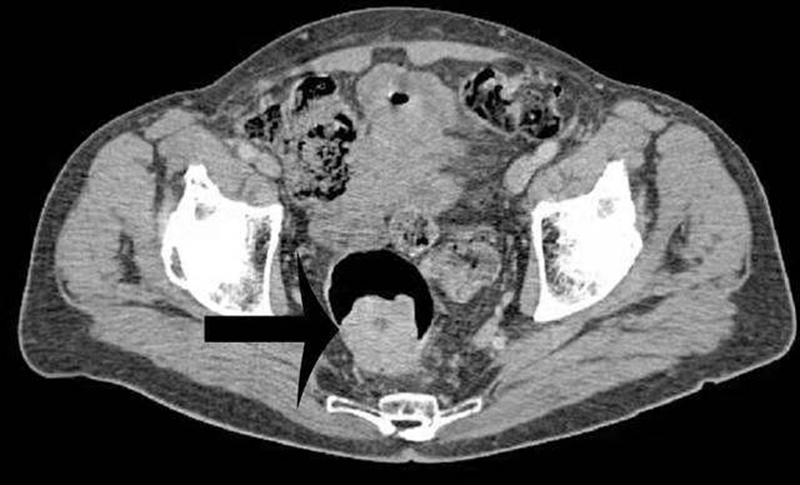

1、影像学检查:如X线胃肠道钡餐造影、CT检查、MRI检查、经直肠超声检查。腹部X线检查适用于伴发急性肠梗阻病人,可见梗阻部位上方的结肠有充气胀大现象。直肠癌术前行直肠MRI为常规检查项目,是术前分期的重要依据。

结肠癌CT

直肠癌CT

肠癌肝转移CT